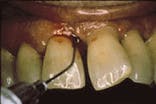

The application of Atridox is shown at the beginning of treatment (left) and four months later (right).